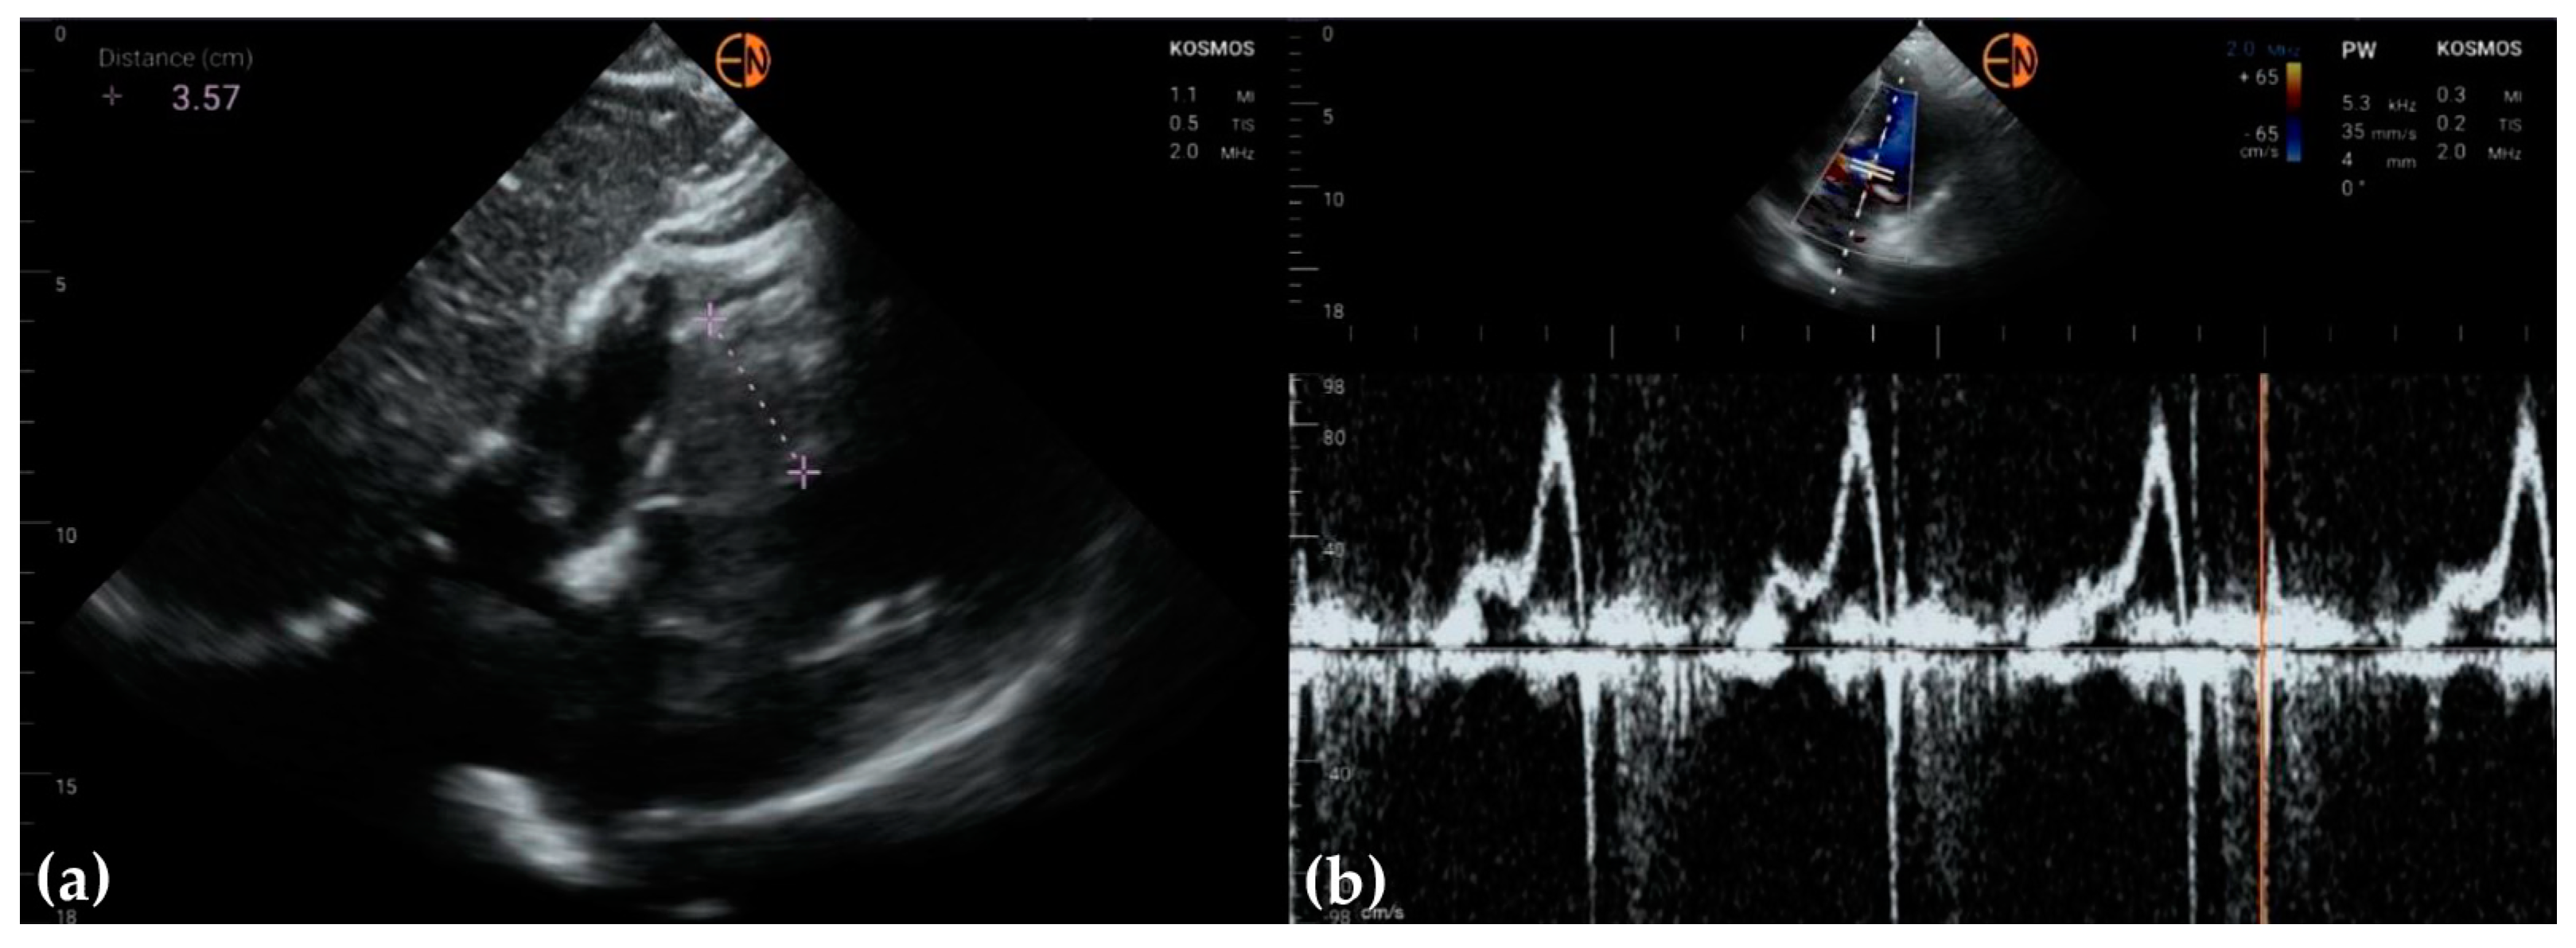

| Ao (mm) | mean (stdev) | 34 (3.8) | 34.4 (4) | −0.38 (2.26) | −0.4 [−4.8 to 4.1] |

| median [Q1 to Q3] | 35 [32 to 36] | 35 [32.3 to 36] | −0.5 [−2 to 1] | ||

| {min to max} | {24 to 41} | {25 to 43} | {−4 to 5} | ||

| LA (mm) | mean (stdev) | 39.2 (5.9) | 39.5 (5.8) | −0.33 (3.28) | −0.3 [−6.8 to 6.1] |

| median [Q1 to Q3] | 39 [35 to 42] | 39.5 [36.3 to 44] | 0 [−3 to 2.75] | ||

| {min to max} | {25 to 50} | {28 to 51} | {−7 to 5} | ||